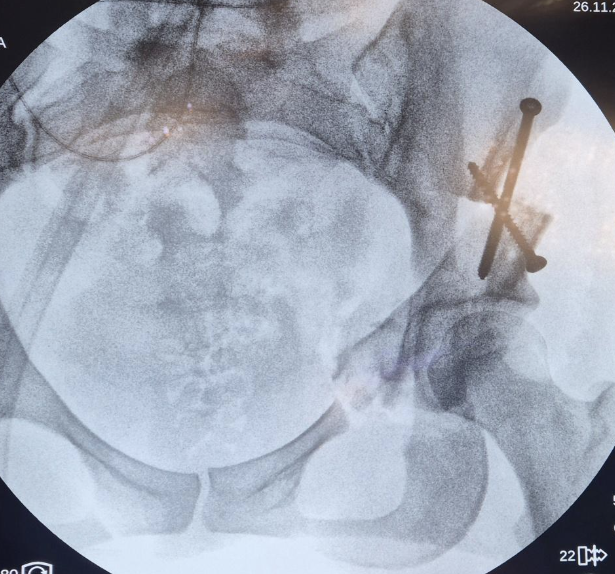

L’intervention est réalisée sous anesthésie générale, par une voie d’abord antérieure. Plusieurs ostéotomies sont réalisées autour du cotyle, qui est ensuite mobilisé, réorienté avec précision, puis fixé par des vis.